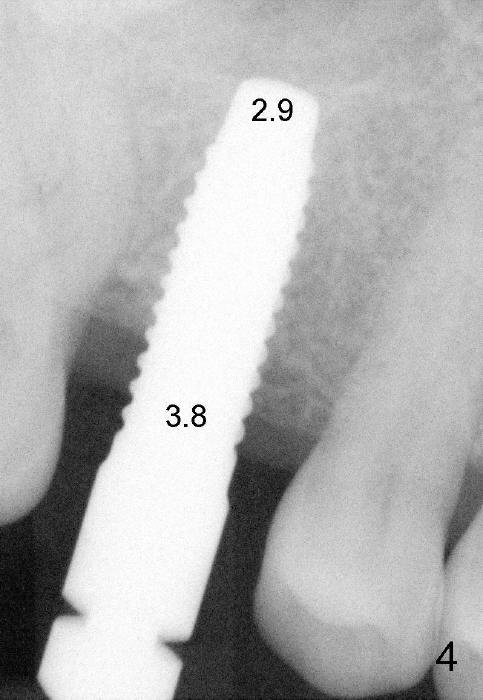

The 42-year-old lady is a dental phobic. The tooth #3 (residual root) is extracted 3.5 years ago. Finally she returns for implant (Fig.1). The mesiodistal space allows to place a 5x14 mm implant (Fig.2). Bone density is felt low when a 1.6 mm pilot drill is used. Bone condensation proceeds with bone expanders 2.6 mm (Fig.3) to 3.8 mm (Fig.4) 12 mm deep. Bone density is felt to increase with each larger expanders. When a 4x11 mm implant is placed (Fig.5), the insertion torque is 15 Ncm. When the diameter and length of the implant increase (Fig.6), the insertion torque is >60 Ncm. To have primary stability, the implant should be two sizes larger than the last expander (compare Fig.4,6)! In addition, the majority portion of the expanders is cylindrical (Fig.3,4), whereas the implant is tapered (Fig.5,6).